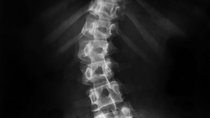

Wenn man von hinten auf die Wirbelsäule schaut, dann sieht sie normalerweise gerade aus. Bei einer Skoliose ist die Wirbelsäule zur Seite verbogen.

Wenn man von hinten auf die Wirbelsäule schaut, dann sieht sie normalerweise gerade aus. Bei einer Skoliose ist die Wirbelsäule zur Seite verbogen. Bei einer rechts-konvexen Skoliose gibt es eine...

Wenn man von hinten auf die Wirbelsäule schaut, dann sieht sie normalerweise gerade aus. Bei einer Skoliose ist die Wirbelsäule zur Seite verbogen. Bei einer links-konvexen Skoliose gibt es eine...

Wenn man von hinten auf die Wirbelsäule schaut, dann sieht sie normalerweise gerade aus. Bei einer Skoliose ist die Wirbelsäule zur Seite verbogen. Bei einer Lumbalskoliose ist die...

Rechtsskoliose bedeutet, dass die Wirbelsäule zur rechten Seite verbogen ist. Wenn man von hinten auf die Wirbelsäule schaut, dann sieht sie normalerweise gerade aus. Bei einer Skoliose ist die...

Wenn man von hinten auf die Wirbelsäule schaut, dann sieht sie normalerweise gerade aus. Bei einer Skoliose ist die Wirbelsäule zur Seite verbogen. Bei einer Rotationsskoliose sind die Wirbel...

Wenn man von hinten auf die Wirbelsäule schaut, dann sieht sie normalerweise gerade aus. Bei einer Skoliose ist die Wirbelsäule zur Seite verbogen. Bei einer Torsionsskoliose ist die Wirbelsäule...

Wenn man von hinten auf die Wirbelsäule schaut, dann sieht sie normalerweise gerade aus. Bei einer Skoliose ist die Wirbelsäule zur Seite verbogen. Bei einer Sinistroskoliose zeigt der Bauch der...

Wenn man von hinten auf die Wirbelsäule schaut, dann sieht sie normalerweise gerade aus. Bei einer Skoliose ist die Wirbelsäule zur Seite verbogen. Bei einer Dextroskoliose zeigt der Bauch der...